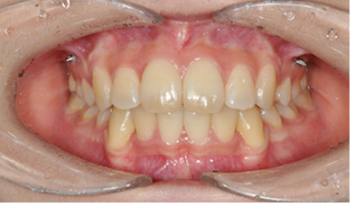

음식을 씹는 기능이 좋아집니다.

칫솔질이 잘 되어 충치나 잇몸 질환이 예방되어 구강 위생이 좋아집니다.

턱뼈의 성장을 조절하여, 주걱턱, 무턱, 비대칭 턱을 해소할 수 있습니다.

얼굴 모양에 좋지 않은 나쁜 습관을 교정해 줌으로써 입 모양이 좋아집니다.

근육 기능이 정상화되면 이갈이, 이 악물기가 줄고 치아 마모도 감소합니다.